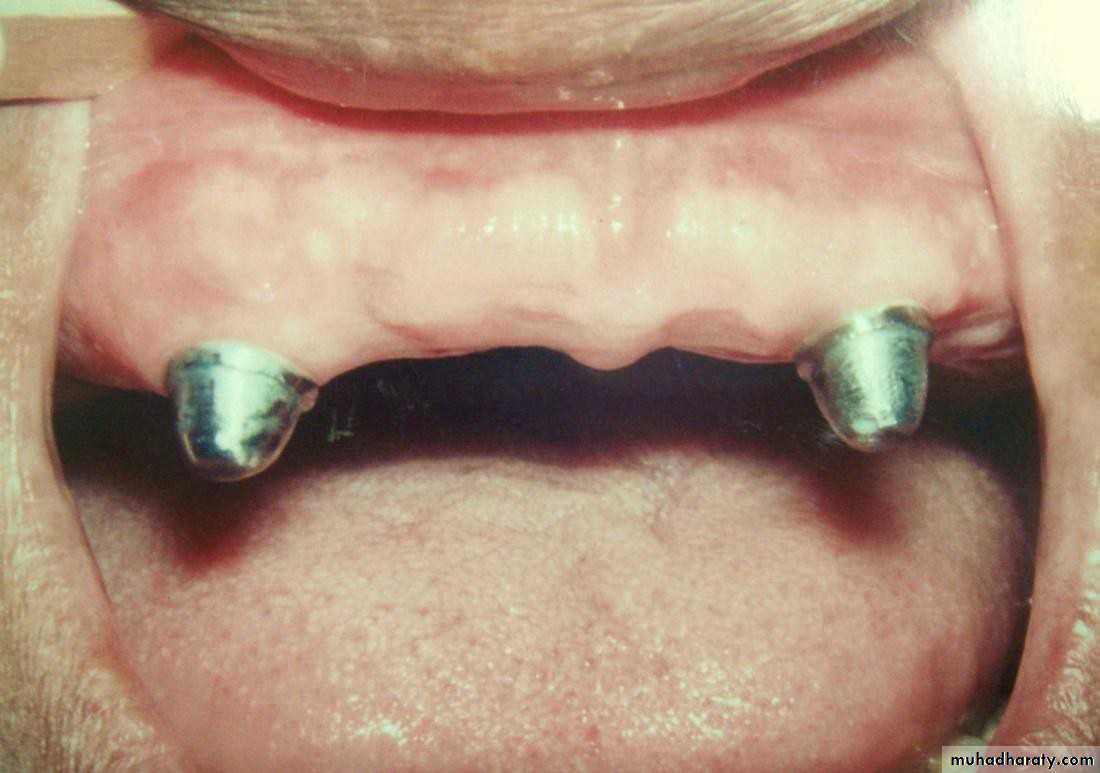

• 3) Medium short (2-4mm):

• a) proximal walls should be parallel for max. frictional fit• b) adjacent abutments better to be splinted

• c) tooth is non vital

• d) used when a favourable C/R ratio

• is needed

• 4) Short (1-2mm):

• a) conform to the curvature of the alveolar ridge (Dum-shape).• b) very low profile.

• c) indicated for max. favourable C/R

• ratio.

• d) can be used with the stud

• attachment.